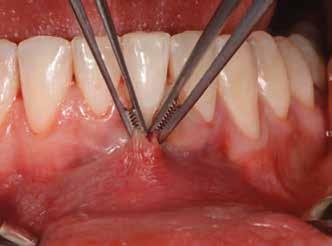

1. ábra: Műtét előtti fogászati panorámafelvétel, amelyen a hiányzó felső állcsont jobb első premolárisát és a szabad véggel rendelkező hidat láthatjuk. — 2. ábra: Az implantátum méreteinek megtervezése CBCT-vel. 3. ábra: Bukkális lágyrészdefektus. — 4. ábra: A biológiai szélesség értékelése a vertikális lágyszövetvastagság alapján. 5. ábra: Palatinális „tekercslebeny” – Palatal roll flap. — 6. ábra: Bredent medical copaSKY 4x10 implantátumbeültetés. 7. ábra: Szubkresztális implantátumbeültetés a várható biológiai szélességnek megfelelően.

8. ábra: Egyéni ínyformázó titánbázison, tulipán alakú emergenciaprofillal. — 9. a. ábra: A sebzárás okkluzális nézete.

Az eljárást helyi érzéstelenítés mellett végeztük (4%-os articaine-hidroklorid 1:100 000 adrenalinnal). Papillakímélő, U alakú palatális bemetszést végeztünk, teljes vastagságú nyálkahártyalebeny preparálás történt, a lebenyt bukkálisan feltekertük (5. ábra). A lebeny bukkálisan feltekert részén de-epitelizációt végeztük el, amellyel kompenzálni tudtuk a bukkális lágyszöveti defektust. Szakaszos előfúrást végeztünk, és a bredent copaSKY 4x10 implantátumot 30 Ncm behajtási nyomatékkal helyeztük be (6. ábra). Az implantátumot 1 mm-re szubkresztálisan helyeztük be, hogy később szélesebb emergenciaprofilt tudjunk kialakítani (7. ábra). Az egyedi ínyformázó úgy készült, hogy kompozitot vittünk fel a titánbázisra, és így formáztuk a lágyszöveteket a transzgingivális gyógyulási fázis során (8. ábra). Az egyéni ínyformázó tulipán formájú, hogy kialakítsa a kívánt emergenciaprofilt. A lágyszövetet feszülésmentesen zártuk #6/0 nem felszívódó, monofil fonallal (Optilene, B. Braun Deutschland; 9. a–b. ábra). Posztoperatív röntgenfelvétel készült, ami alapján az implantátum a szomszédos fogakkal párhuzamos elhelyezést mutatott (10. ábra). Posztoperatív utasításokat adtunk a páciensnek a műtéti terület körüli szájhigiénia fenntartása érdekében. A beavatkozást követő egy héttel a varratokat eltávolítottuk, és a kezelt terület kielégítő gyógyulást mutatott (11. ábra). A 4 hónap utáni késleltetett terhelést a páciens kívánsága szerint terveztük.